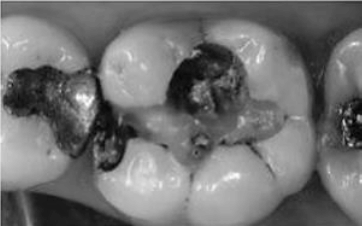

Observe a imagem a seguir:

A restauração do dente 36 é classificada como: